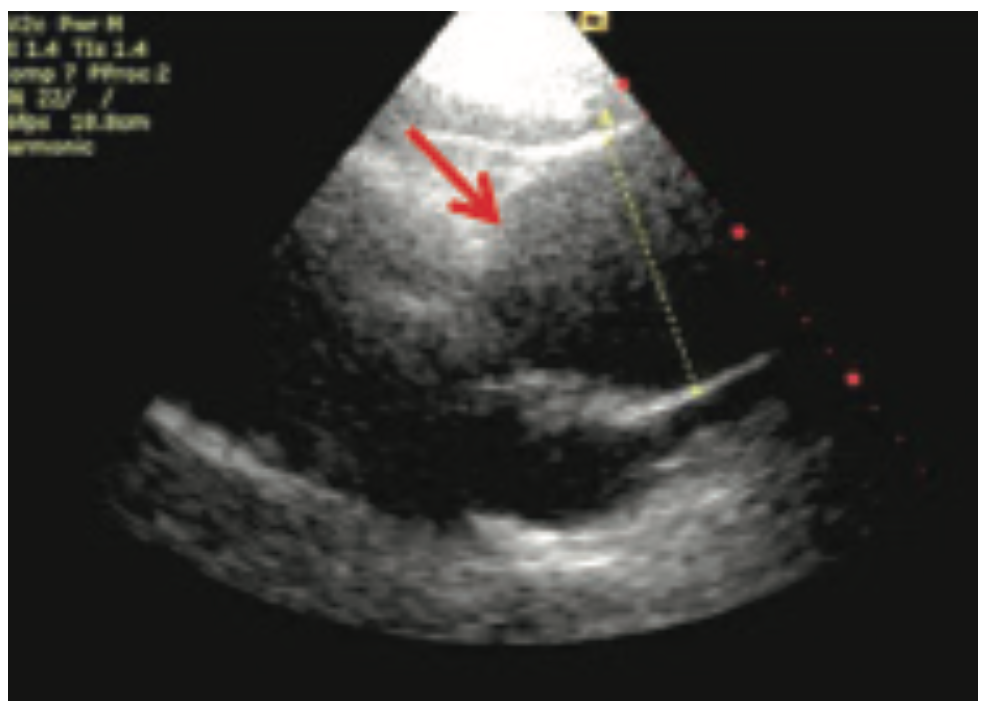

She was widowed, lived alone, and quit smoking 4 years ago, with a 40 pack-year smoking history. Her family history was non-contributory. She had noticed some dyspnea on exertion during routine chores such as mowing the lawn and carrying laundry upstairs, which she attributed to deconditioning. She was otherwise asymptomatic, even during her episode of supraventricular tachycardia (SVT) during her recent colonoscopy. During her TTE, the technologist notified the cardiologist of a 9-centimeter ascending aortic aneurysm, effacing the sinotubular junction with dilated sinuses of Valsalva. The TTE also demonstrated moderate aortic regurgitation. There was no evidence of vegetation or aortic dissection, or pericardial effusion. The patient was admitted to the University Hospital from the office for further management. A computed tomography scan of the chest with contrast was done in the emergency department to further define the aneurysm. Cardiac catheterization was performed the following day, revealing normal coronaries, normal left ventricular systolic function, and a 9-centimeter ascending aortic aneurysm. She underwent urgent cardiothoracic surgery. The surgeon repaired her aortic root with a Dacron patch and replaced her aortic valve with a bioprosthetic pericardial aortic valve. The patient had an otherwise unremarkable post-operative course, primarily consisting of blood pressure control. She was discharged with surgical follow-up within 1 week and cardiology follow-up in 2 weeks.